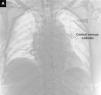

Accidental cannulation of the aortic arch with a central venous catheter

Canalización accidental del cayado aórtico con un catéter venoso central